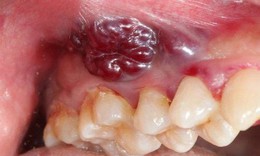

Dấu hiệu điển hình của ung thư khoang miệng ở giai đoạn sớm

Dấu hiệu cảnh báo ung thư khoang miệng

Ung thư - 08/06/2024 09:09SKĐS - Ung thư khoang miệng là một tổn thương ác tính xuất hiện tại vùng khoang miệng bao gồm: lưỡi, lợi hàm dưới, niêm mạc má, sàn miệng, lợi hàm trên, khẩu cái và môi.

Chủ quan với vết loét miệng do nghiện hút thuốc lá, người đàn ông ở Hà Nội tá hoả khi bị ung thư

- 06/03/2019 07:00SKĐS - Thấy miệng có vết loét nhỏ, người đàn ông 60 tuổi ở Hà Nội cứ nghĩ là bị nhiệt nên đã không điều trị gì. Tuy nhiên, khi chỗ loét dày, to lên nhanh và hơi cứng , ông mới đi thăm khám thì bác sĩ cho biết đã bị ung thư khoang miệng giai đoạn 2